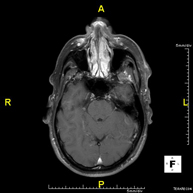

- Neurorradiología

- RM Cerebral (craneal)

Prueba diagnóstica no invasiva que consiste en la obtención de imágenes de alta definición anatómica del cerebro mediante el empleo de un campo electromagnético y ondas de radio (con un emisor y un receptor). No utiliza radiación ionizante. Indicaciones: problemas vasculares, pérdida de memoria, epilepsia, cefalea, malformaciones, sospecha de tumor, meningitis.